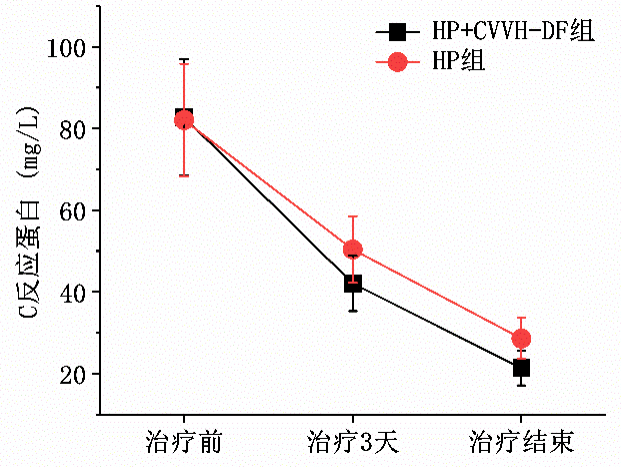

血液灌流聯合其他血液凈化治療方式時,能夠有效糾正患者內環境紊亂,改善其生命體征,預防后續并發癥的發生。例如,血液灌流(HP)聯合連續性血液透析濾過(CVVH-DF)治療可糾正患者體內微環境狀態,改善患者預后。[5]

圖3 急性重度有機磷中毒患者不同治療方式后的C反應蛋白濃度